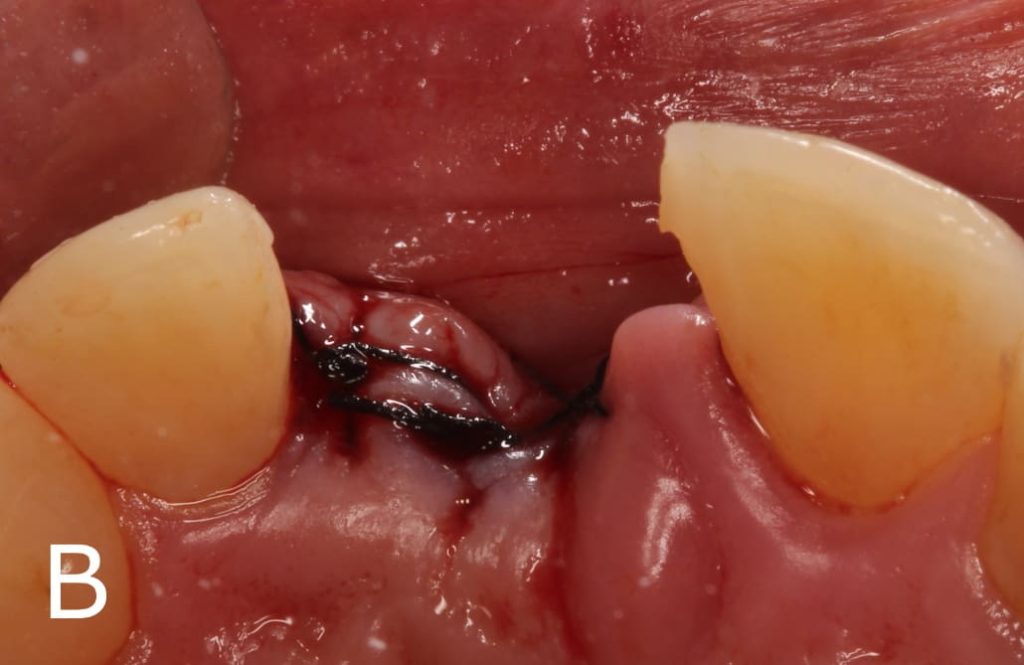

Después de realizar la preparación, grabe con ácido fosfórico al 37% (Angelus Industria de Productos Odontológicos S/A, Paraná, Brasil) durante 30 segundos (Figura 2A), lavar por el mismo tempo y luego secar com chorro de aire. Luego aplique dos capas de adhesivo (Angelus Industria de Productos Odontológicos S/A, Paraná, Brasil) (Figura 2B) y 2 fotopolimerizar por 30 segundos (Figura 3). Después de hibridar los dientes pilares, realizar la preparación del diente, en este caso se utilizó el diente del propio paciente, realizando un desgaste en la región palatina para que el Interlig tenga espacio suficiente para asentarse sobre este diente, y quede completamente cubierto por la resina compuesta. El Interlig ya es uma fibra silanizada e impregnada, por lo que no requiere ningún tipo de tratamiento previo a su uso, basta com cortarlo al tamaño adecuado (Figura 4). Después de realizar el desgaste, use ácido fosfórico al 37 % y adhesivo en el diente de stock, preparándolo para realizar la adhesiva directa.